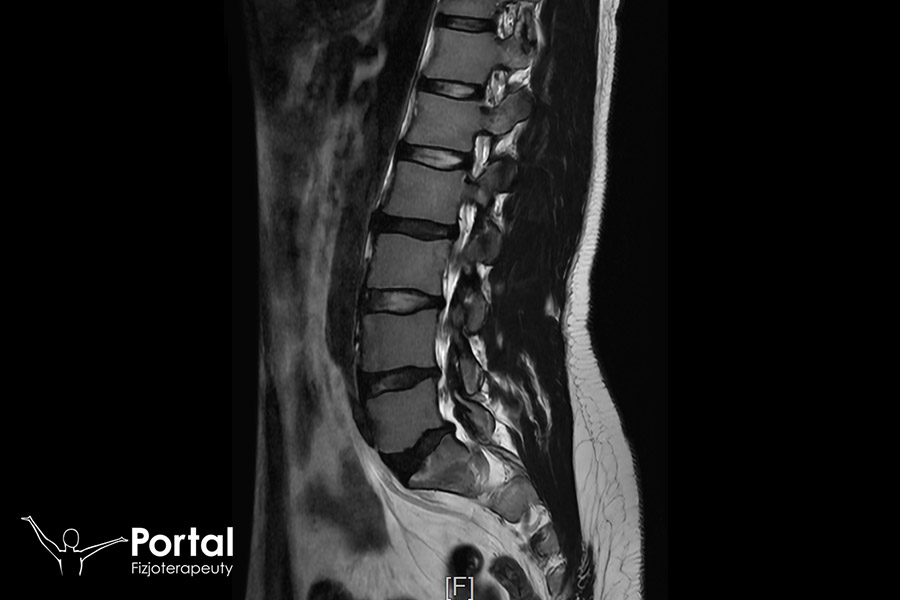

Kolana szpotawe to wada postawy, w której oś podudzia tworzy z osią uda kąt otwarty do wewnątrz. Odległość między kolanami w staniu ze złączonymi kostkami przyśrodkowymi wynosi powyżej 4 cm. Wada ta nasila się w okresie rozwoju i wzrostu organizmu (wiek szkolny). Przyjmuje się, że ma swój początek pomiędzy 1 a 3 rokiem życia. Jest wówczas zjawiskiem fizjologicznym, które zanika około 4 roku życia. Zwykle dotyczy obu kończyn dolnych. Wada obejmująca wyłącznie jedną kończynę dolną jest wskazaniem do badania radiologicznego.

Inną przyczyną może być przebyte zapalenie kości, choroba Blounta lub doznany uraz. Warto także prześledzić choroby występujące w rodzinie.